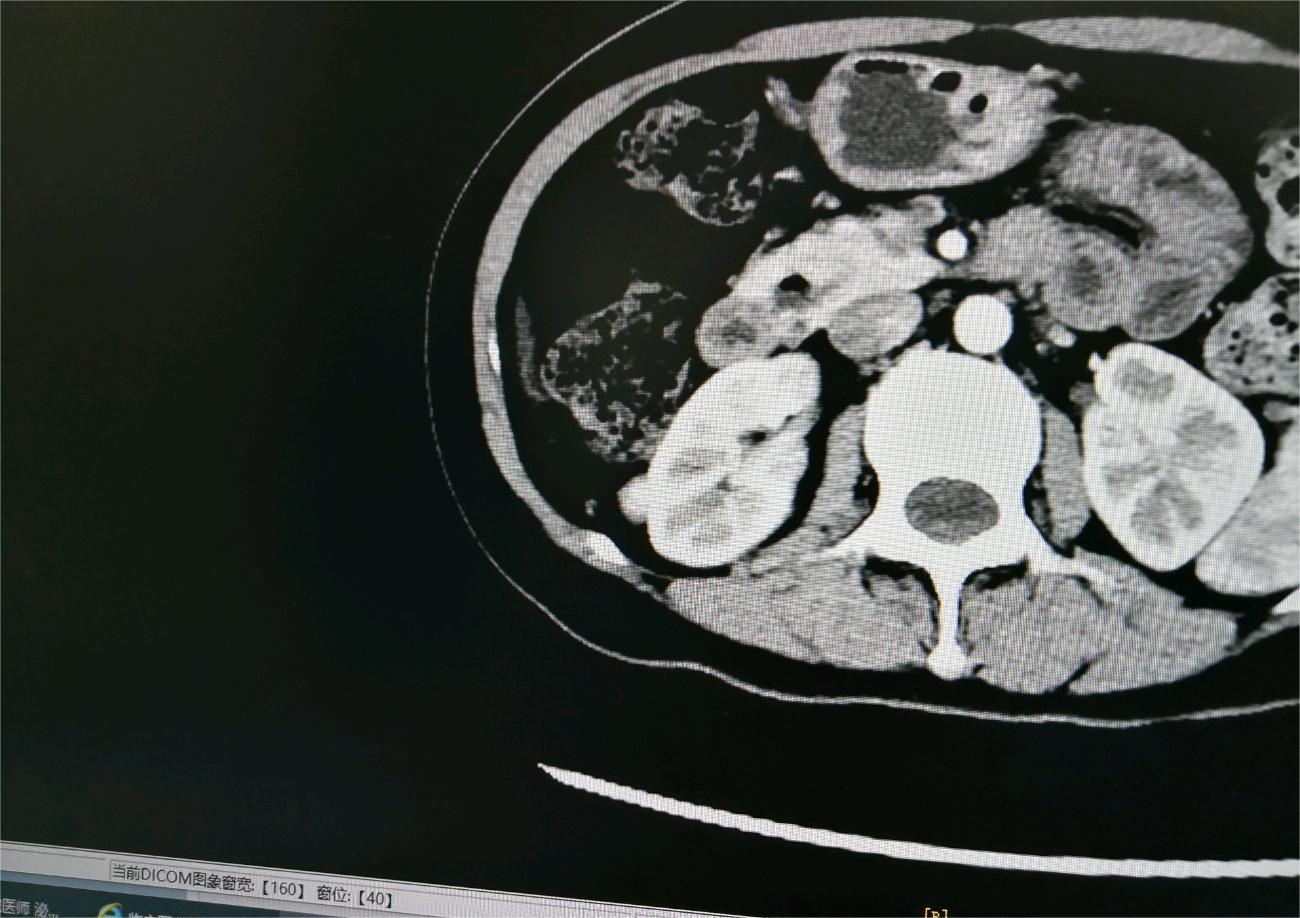

起风了 02025-09-08 患者家属膀胱癌4期尿路上皮癌伴鳞状分化,膀胱全切除后化疗4期(GC方案)加一期免疫替雷利珠单抗,复查增强Ct已转移肝脏和腹腔内壁...